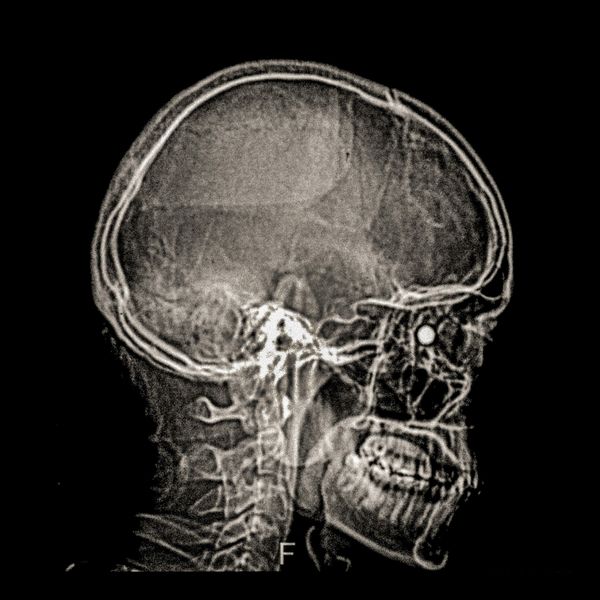

460 people have been seriously injured in their eyes, 34 of whom suffered total loss due to the indiscriminate use of pellets and tear gas bombs by the Carabineros de Chile special forces. The Carabineros fired their rubber bullets and tear gas guns directly into the faces of the protesters during the Chilean social outbreak between late 2019 and early 2020. This figure has made Chile the country with the world record for eye mutilation by state and security forces.

By early March 2020, around 3,838 people had been injured and according to the Chilean Society of Ophthalmologists and human rights organizations, 460 of them ended up with serious eye complications, loss of the eyeball, and also loss of sight. This figure has made Chile a world record for eye mutilation, due to the indiscriminate use of pellets and tear gas bombs by special forces of the Carabineros, who have shot their weapons directly into the faces of the protesters.